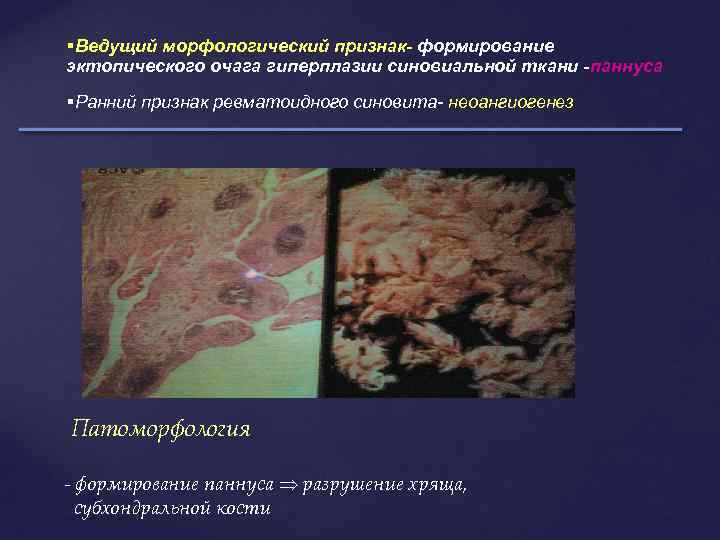

Ведущий морфологический признак- формирование эктопического очага гиперплазии синовиальной ткани -паннуса Ранний признак ревматоидного синовита- неоангиогенез Патоморфология - формирование паннуса разрушение хряща, субхондральной кости

Ведущий морфологический признак- формирование эктопического очага гиперплазии синовиальной ткани -паннуса Ранний признак ревматоидного синовита- неоангиогенез Патоморфология - формирование паннуса разрушение хряща, субхондральной кости